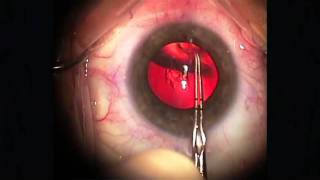

Five Steps to More Consistent Cataract Surgery video

Five Steps to More Consistent Cataract Surgery

Five Steps to More Consistent Cataract Surgery